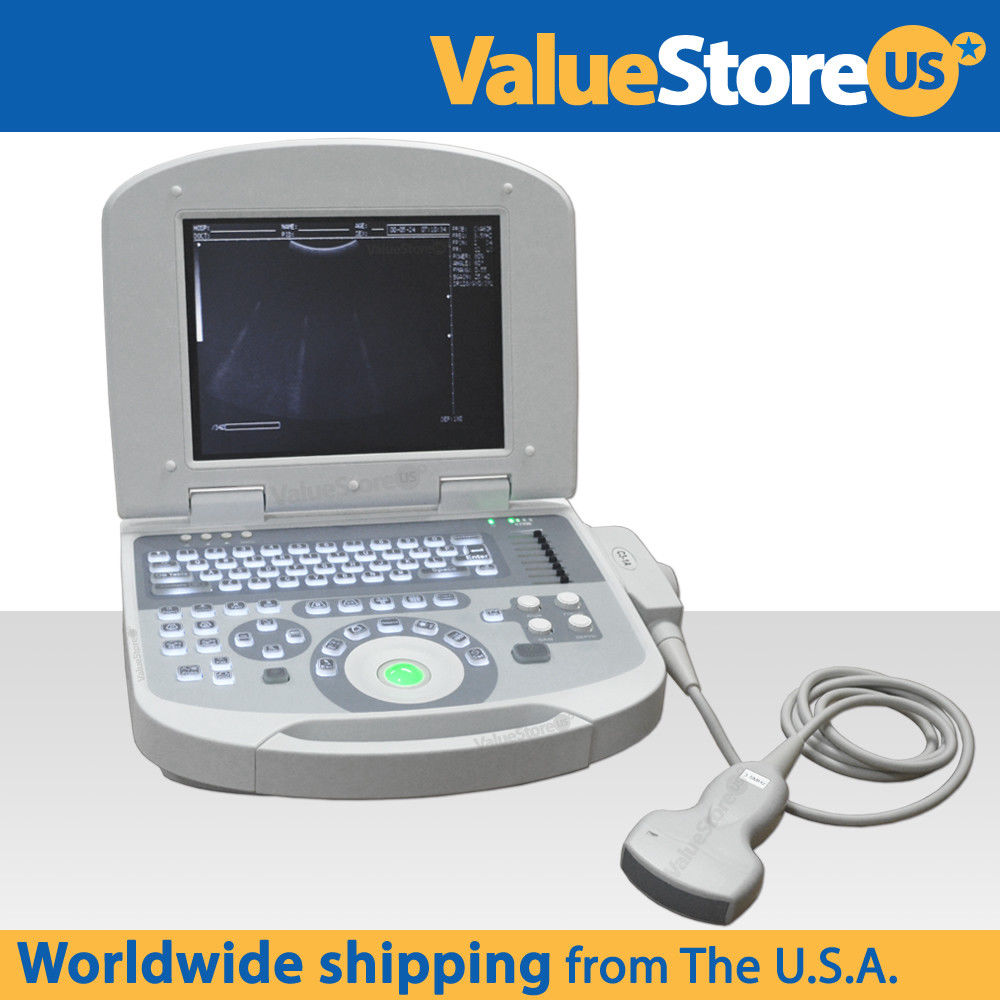

Ultrasound Scanner Laptop Machine Ultrasonic Machine Convex Rectal Transducer